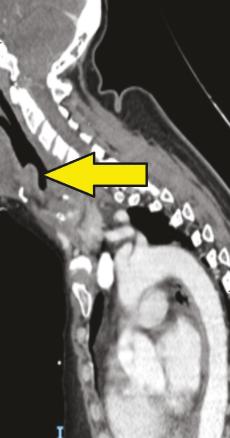

Une patiente de 56 ans se présente aux urgences avec un tableau fébrile à 39 °C évoluant depuis vingt-quatre heures, associant odynophagie et dyspnée. Elle est polypnéique à 25 cycles/min et désature à 89 %. Elle est assise, bouche ouverte avec une hypersialorrhée, dysphonique. La palpation cervicale est douloureuse, sans cellulite ni emphysème. L’ORL se déplace rapidement pour réaliser une nasofibroscopie, qui confirme le diagnostic d’épiglottite non abcédée. À sa demande, un scanner cervical injecté est réalisé sans allonger la patiente. Il retrouve un épaississement pariétal circonférentiel sténosant de la paroi laryngée responsable d’une réduction du calibre de la lumière laryngée d’environ 70 % (fig. 1 et 2 ).